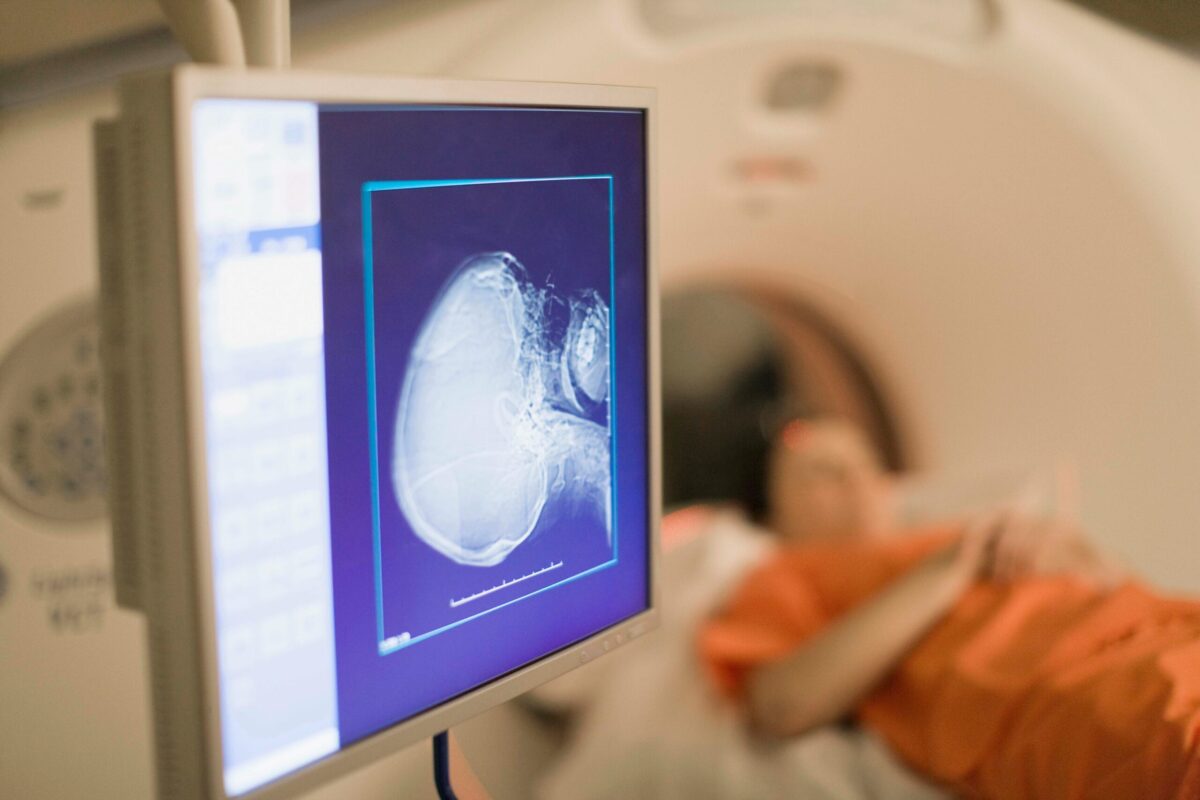

Brain scan

Brain health is the next frontier in longevity.

Early warning. Quest Diagnostics now offers Alzheimer’s blood tests, improving access while decreasing reliance on costly PET scans.

Scaling screenings, MYndspan is pioneering an MEG clinic, Belfast’s Cumulus Neuroscience launched a three-minute EEG, and Prenuvo flags presymptomatic brain changes.